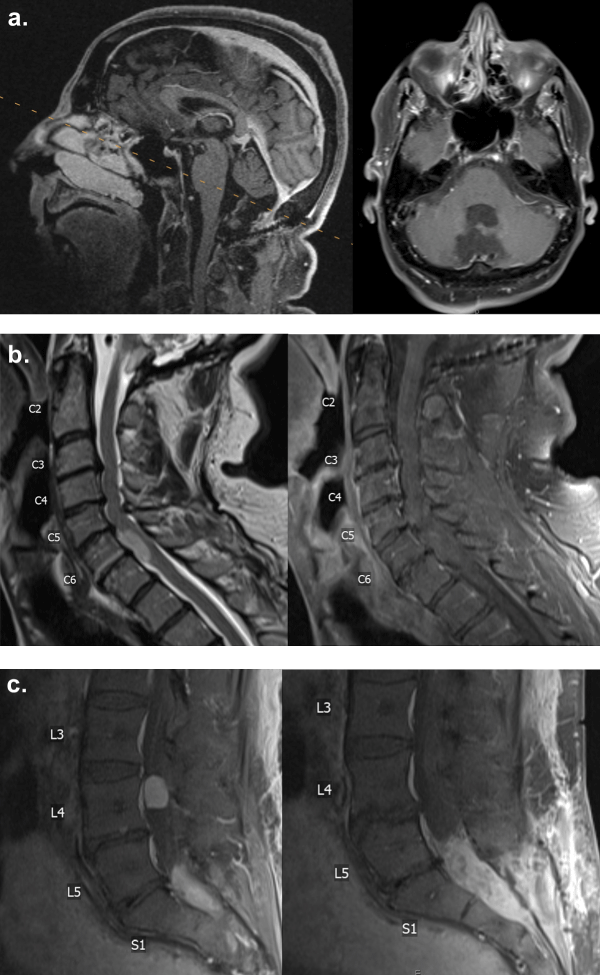

Less than two years after the sacral lesion biopsy, when the patient was 58 years old, he reported progressive weakness in his left arm and leg without numbness or tingling, though he endorsed some loss of vibration sensation in his left leg. He denied radiating pain in his extremities, saddle anesthesia, or bowel or bladder problems but reported experiencing urinary incontinence 3-4 months ago. Slight muscle weakness was observed in his left upper extremity in addition to weakness in left hip flexion and knee extension. MRI of the cervical spine revealed an intradural anterior lesion at the C6-7 level, eccentric to the left, measuring 2.2 cm in superior-inferior dimension, representing a 5.4 mm increase from the original size (Figure 2a and Figure 2b). The lesion occupied more of the spinal canal and caused a more significant mass effect on the spinal cord compared to the MRI two years prior. An open biopsy of the C6-7 lesion was proposed, as this lesion did not enhance, in contrast to the L4 and sacral lesions. It was unclear at this time whether the lesion was consistent with disseminated ependymoma. A C6-7 laminectomy was performed, and a small portion of the accessible tumor on the right side was obtained for pathology. We did not believe it was possible or safe to retract the spinal cord to attempt resection of the tumor from a posterior approach. The soft mass was consistent with low-grade ependymoma. No intraoperative or immediate postoperative complications were observed.

Figure 2: T2-weighted MRI demonstrating a hyperintense lesion without contrast enhancement at the C6-7 level anterior to the spinal cord, (a): At initial diagnosis measuring 16.9 mm in superior-inferior dimension; (b,c): Two years after initial diagnosis measuring 22.3 mm in superior-inferior dimension. View Figure 2

The patient returned to the clinic for a 1.5-month postoperative follow-up. MRI of the cervical spine taken after the biopsy continued to show a non-enhancing intradural anterior lesion at the C6-7 level, eccentric to the left. A C5-7 corpectomy for resection of the intradural extramedullary ependymoma would avoid displacement of the spinal cord, allowing for exposure of the tumor while visualizing the anterior vasculature of the spinal cord. It was also unclear whether the tumor was adherent to the anterior aspect of the spinal cord. Due to the cervical spinal cord covering nearly the entire tumor posteriorly, we did not believe a posterior approach was safe (Figure 2c). The operation was high-risk but was considered beneficial to the patient as the progressive weakness in his left upper and lower extremities would likely continue without surgical resection of the tumor. An extensive discussion was conducted with the patient and his wife, who elected to proceed with an anterior approach for cervical ependymoma resection, followed by a stage two, posterior spinal fusion, involving C2 to T3.